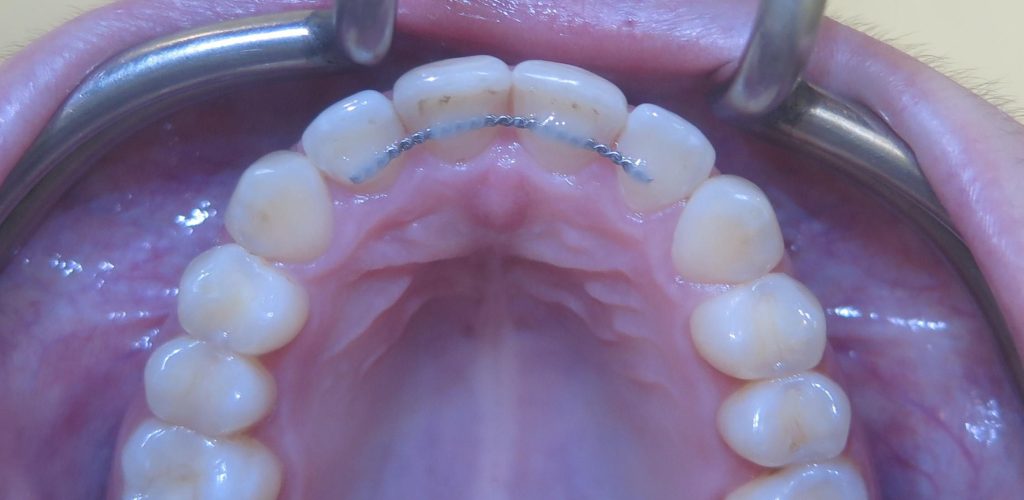

Cała terapia, jak zawsze w takich przebudowach, nawet częściowych wiąże się z bezwzględnym zwieńczeniem wykonania szyny ochronnej, której konstrukcja jest zawsze uwarunkowana indywidualnie. Zalecenia jej noszenia przez lekarza również są indywidualne i mogą się zmieniać w perspektywie czasu.

Tak wyprowadzony Pacjent powinien stawiać się (oczywiście zawsze z szyną) na wizytach kontrolnych co 6 m-cy. W międzyczasie z zaleceń lekarza z pewnością wskazane mogą być zabiegi higienizacyjne u naszych Pań higienistek, by podtrzymać u Pacjenta zdrowy stan przyzębia.